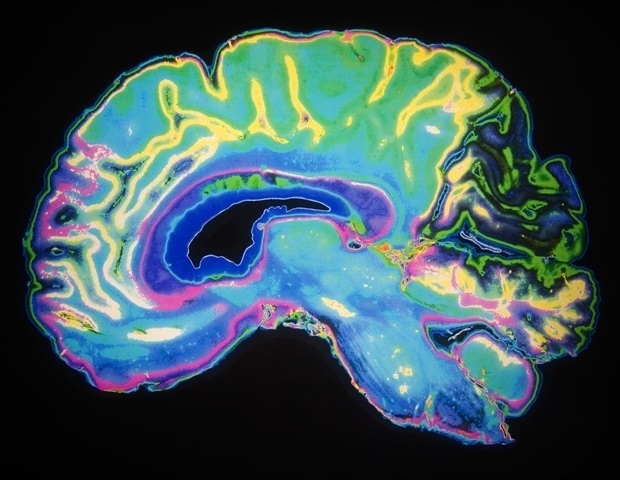

‘A second set of eyes’: AI-supported breast cancer screening spots more cancers earlier, landmark trial finds

Science

Really Simple SyndicationFebruary 7, 2026

A clinical trial shows that AI-assisted mammography can detect more cases of dangerous cancer and reduce missed diagnoses.